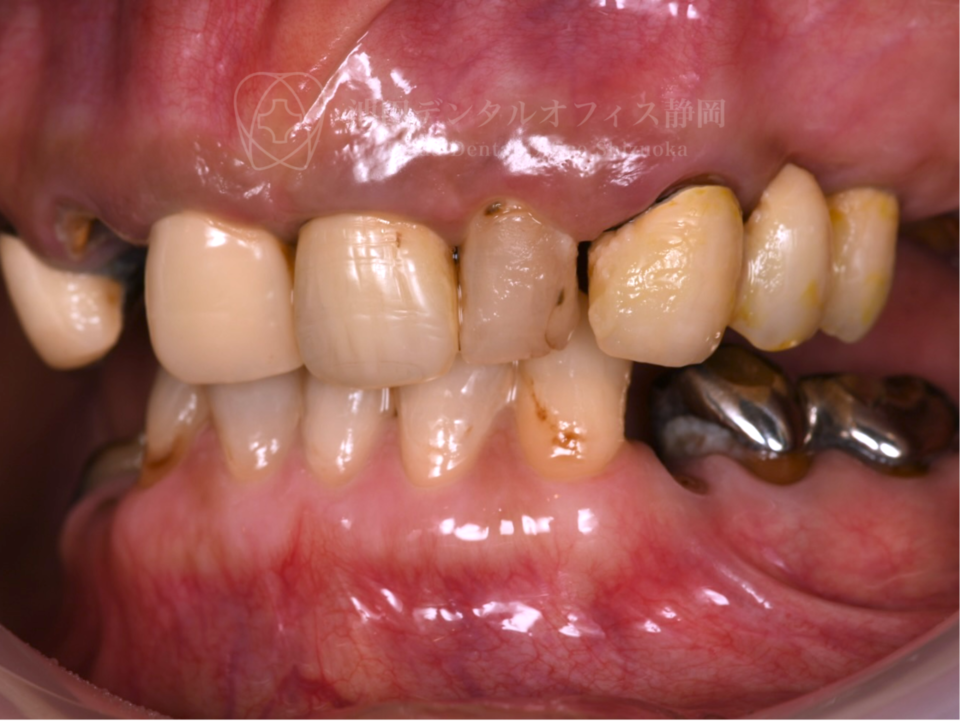

過去にいろんな歯医者で部分的な治療を受けた結果、噛み合わせがずれ様々な問題を抱えていた患者さんです。全体の治療を決意され、他県から新幹線を乗り継いで通院していただきました。